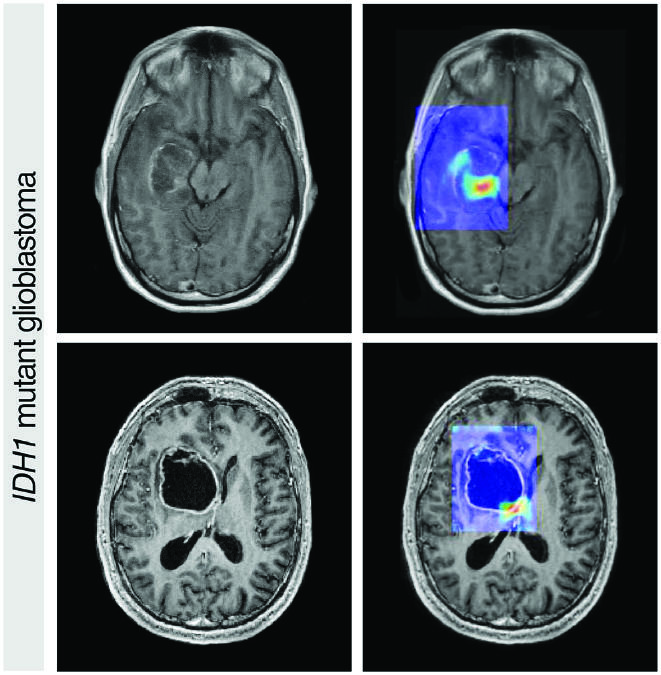

- Radiology: AI algorithms can scan X-rays, MRIs, and CT scans to identify potential issues. The Nature study highlights AI's role in improving radiological diagnostics.

- Pathology: AI models help in analyzing tissue samples for cancerous cells.